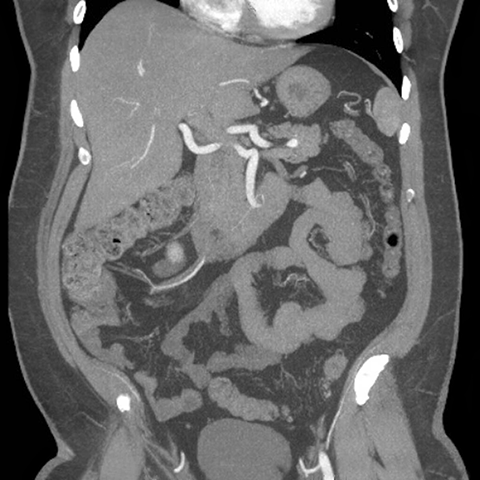

Abdominal Wall Muscles Normal Anatomy, Coronal CT [8 of 9]